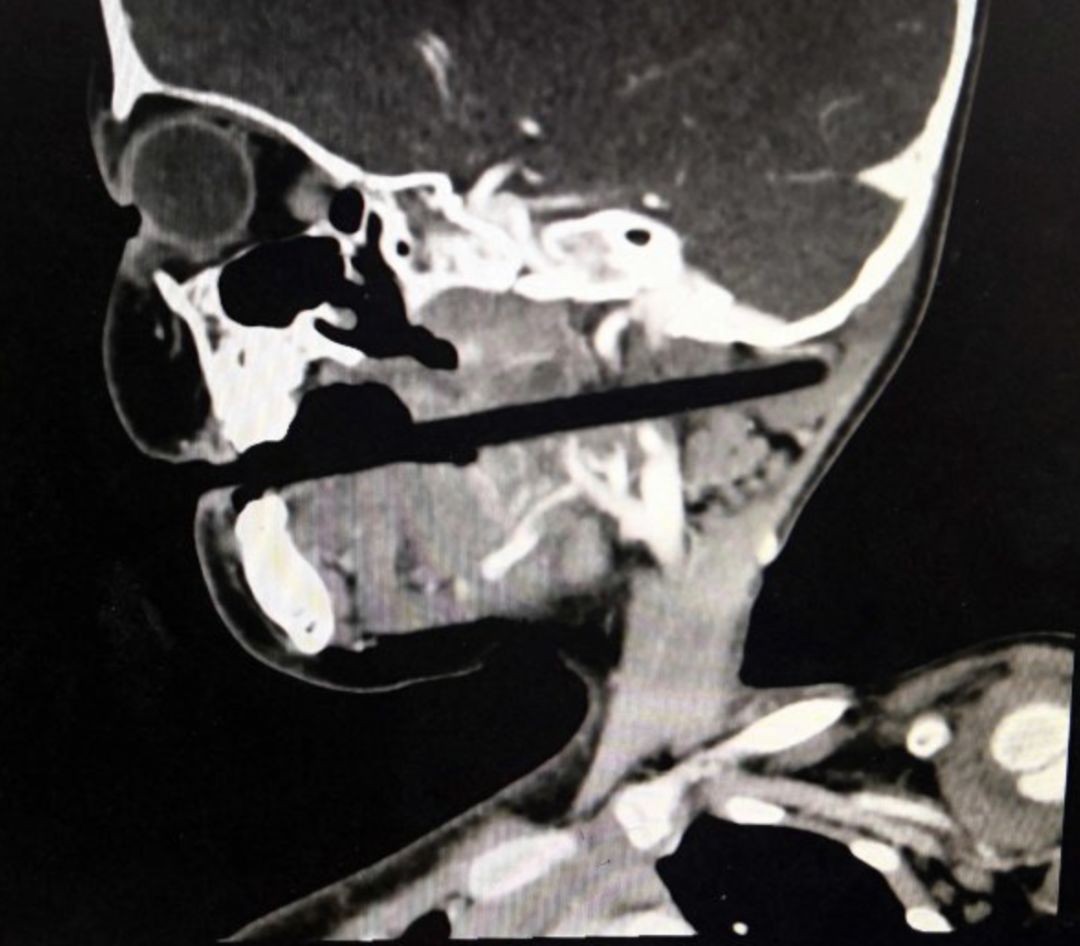

3岁孩子拿着筷子乱跑跌倒,筷子插入颅内10厘米……

1 3岁孩子乱跑不慎跌倒, 筷子插入颅内10厘米……

其实类似的意外已经发生了不少次,搜一搜类似的新闻太多了。说明家长们根本就没有引起重视。孩子用吸管喝牛奶的时候打闹,结果吸管插入眼睛,导致角膜损伤;吃鱼丸时摔跤,筷子直插男童颅底。在儿童意外伤害事件中,不少是走路摔跤,异物插到脸部或者眼部。

万一发生了意外,医生也提醒,家长千万要冷静,一定不要将插在孩子脸上的异物拔出,以免二次伤害,应第一时间送医,让医生处理。若发现年幼的孩子将零碎东西含在嘴里,要引导孩子主动吐出,惊吓哭闹中,孩子反而容易把东西吞入。